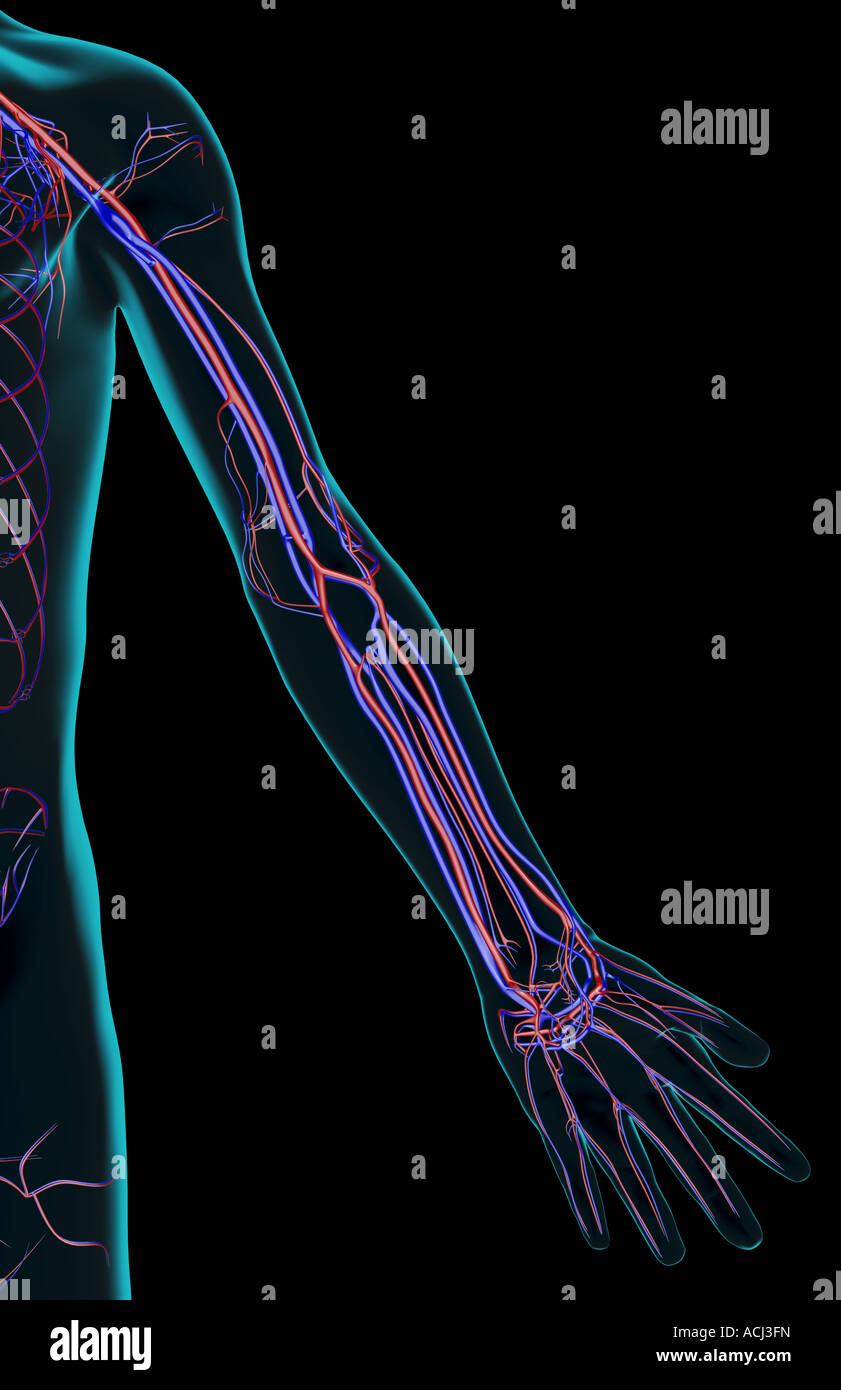

The blood supply of the upper limb Stock Photohttps://www.alamy.com/image-license-details/?v=1https://www.alamy.com/stock-photo-the-blood-supply-of-the-upper-limb-13166120.html

The blood supply of the upper limb Stock Photohttps://www.alamy.com/image-license-details/?v=1https://www.alamy.com/stock-photo-the-blood-supply-of-the-upper-limb-13166120.htmlRFACJ3FN–The blood supply of the upper limb